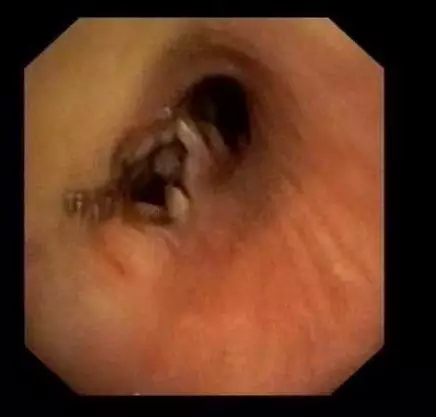

2015.03

咳嗽、咯痰小心食管-支气管瘘 我院为您诊治